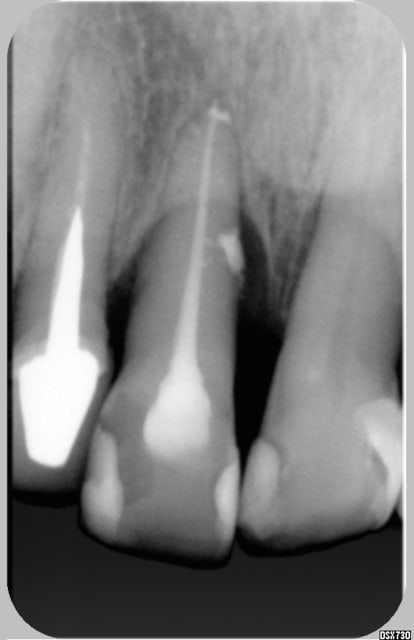

jeff2 ton cas pour moi c'est pas un canal lateral au depart c'est une felure car sur la derniére image il me semble qu'il y a un decrochement en mesial qui est apparu et qui traduit le deplacement Non???. D'ailleurs le parodonte environnant n'est pas stabilisé.......enfin me semble-t -il

Jeff2, ton cas ne correspond pas au mien regarde bien l'image du canal...

canal lat ou fracture? la derniere radio ne Jeff2 ne m'a pas encore convaincu...mais c'est vrai que l'endo est tres belle...

Revue hier, mobilité, nouvelle radio fracture confirmée mais sensibilité -

Sinon à la radio, j'ai plus l'impression d'une lyse apicale que d'une fracture.